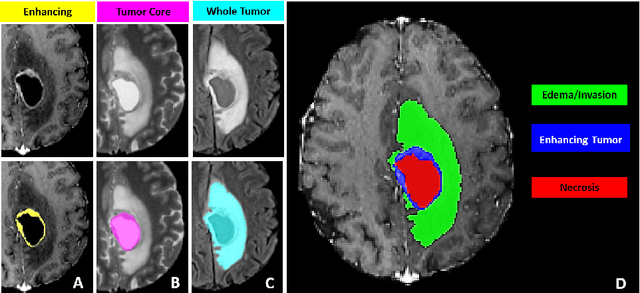

Abstract:The BraTS 2021 challenge celebrates its 10th anniversary and is jointly organized by the Radiological Society of North America (RSNA), the American Society of Neuroradiology (ASNR), and the Medical Image Computing and Computer Assisted Interventions (MICCAI) society. Since its inception, BraTS has been focusing on being a common benchmarking venue for brain glioma segmentation algorithms, with well-curated multi-institutional multi-parametric magnetic resonance imaging (mpMRI) data. Gliomas are the most common primary malignancies of the central nervous system, with varying degrees of aggressiveness and prognosis. The RSNA-ASNR-MICCAI BraTS 2021 challenge targets the evaluation of computational algorithms assessing the same tumor compartmentalization, as well as the underlying tumor's molecular characterization, in pre-operative baseline mpMRI data from 2,000 patients. Specifically, the two tasks that BraTS 2021 focuses on are: a) the segmentation of the histologically distinct brain tumor sub-regions, and b) the classification of the tumor's O[6]-methylguanine-DNA methyltransferase (MGMT) promoter methylation status. The performance evaluation of all participating algorithms in BraTS 2021 will be conducted through the Sage Bionetworks Synapse platform (Task 1) and Kaggle (Task 2), concluding in distributing to the top ranked participants monetary awards of $60,000 collectively.

Abstract:This manuscript describes the first challenge on Federated Learning, namely the Federated Tumor Segmentation (FeTS) challenge 2021. International challenges have become the standard for validation of biomedical image analysis methods. However, the actual performance of participating (even the winning) algorithms on "real-world" clinical data often remains unclear, as the data included in challenges are usually acquired in very controlled settings at few institutions. The seemingly obvious solution of just collecting increasingly more data from more institutions in such challenges does not scale well due to privacy and ownership hurdles. Towards alleviating these concerns, we are proposing the FeTS challenge 2021 to cater towards both the development and the evaluation of models for the segmentation of intrinsically heterogeneous (in appearance, shape, and histology) brain tumors, namely gliomas. Specifically, the FeTS 2021 challenge uses clinically acquired, multi-institutional magnetic resonance imaging (MRI) scans from the BraTS 2020 challenge, as well as from various remote independent institutions included in the collaborative network of a real-world federation (https://www.fets.ai/). The goals of the FeTS challenge are directly represented by the two included tasks: 1) the identification of the optimal weight aggregation approach towards the training of a consensus model that has gained knowledge via federated learning from multiple geographically distinct institutions, while their data are always retained within each institution, and 2) the federated evaluation of the generalizability of brain tumor segmentation models "in the wild", i.e. on data from institutional distributions that were not part of the training datasets.